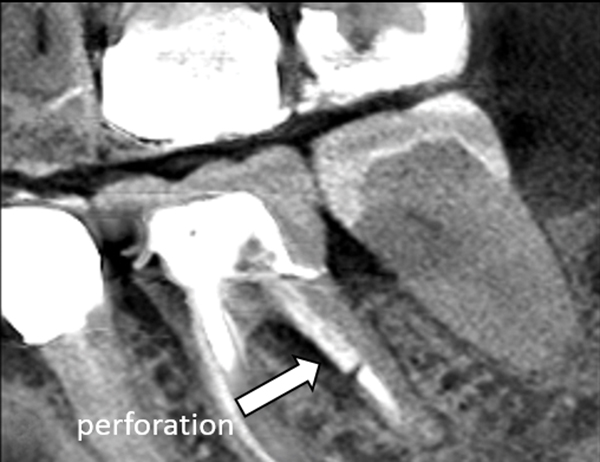

Cone Beam Computed Tomography CBCT has become an indispensable diagnostic imaging tool in clinical endodontics. CBCT is useful in the planning of surgical endodontic procedures as it will provide accurate information as to the size and location of the periapical lesion and root apex in relation to structures such as the maxillary sinus inferior dental canal and mental foramen Figures 6A and 6B. CBCT units reconstruct the projection data to provide interrelational images in three orthogonal planes axial sagittal and coronal.

1- apical morphology and suspected lesions of endodontic region. In the case of endodontics the scotoma is actual tooth structure which our eyes are not capable of seeing through. Endodontics CBCT is a very useful tool in diagnosing apical lesions Crown morphology pulp chamber proximal caries Root morphology number of root canals course and direction of canals accessory canals root resorption root fractures.